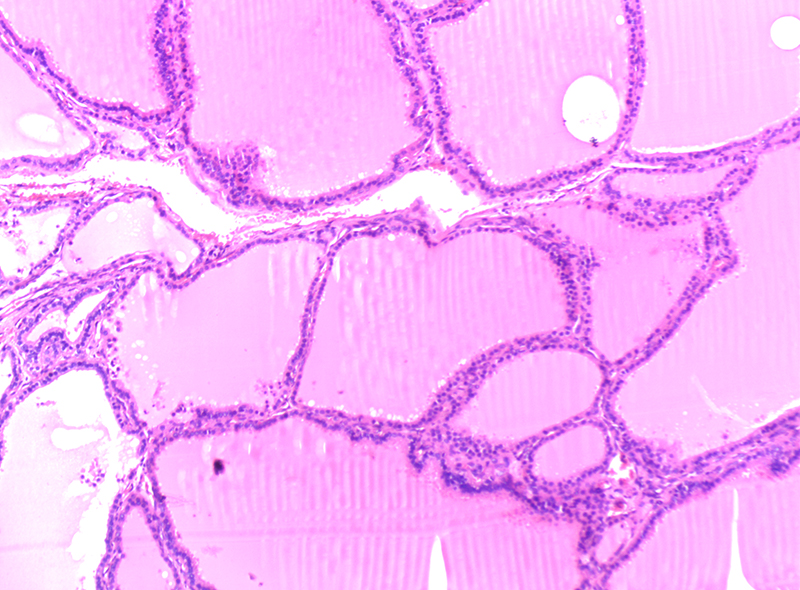

毒性甲狀腺腫